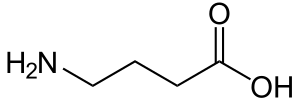

Pain management

Psychoactive drugs are often prescribed to manage pain. The subjective experience of pain is primarily regulated by endogenous opioid peptides. Thus, pain can often be managed using psychoactives that operate on this neurotransmitter system, also known as opioid receptor agonists. This class of drugs can be highly addictive, and includes opiate narcotics, like morphine and codeine.[26] NSAIDs, such as aspirin and ibuprofen, are also analgesics. These agents also reduce eicosanoid-mediated inflammation by inhibiting the enzyme cyclooxygenase.

Psychoactive drugs operate by temporarily affecting a person's neurochemistry, which in turn causes changes in a person's mood, cognition, perception and behavior. There are many ways in which psychoactive drugs can affect the brain. Each drug has a specific action on one or more neurotransmitter or neuroreceptor in the brain.

Drugs that increase activity in particular neurotransmitter systems are called agonists. They act by increasing the synthesis of one or more neurotransmitters, by reducing its reuptake from the synapses, or by mimicking the action by binding directly to the postsynaptic receptor. Drugs that reduce neurotransmitter activity are called antagonists, and operate by interfering with synthesis or blocking postsynaptic receptors so that neurotransmitters cannot bind to them.[51]